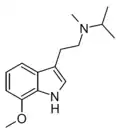

Substituted tryptamines, or serotonin analogues, are organic compounds which may be thought of as being derived from tryptamine itself. The molecular structures of all tryptamines contain an indole ring, joined to an amino (NH2) group via an ethyl (−CH2–CH2−) sidechain. In substituted tryptamines, the indole ring, sidechain, and/or amino group are modified by substituting another group for one of the hydrogen (H) atoms.

| Chemical structure | Short Name | Origin | Ring Substitution | RN1 | RN2 | Full Name | CAS Number |

|---|---|---|---|---|---|---|---|

| 5-MeO-MiPT | artificial | 5-OCH3 | CH3 | CH(CH3)2 | 5-methoxy-N,N-methylisopropyltryptamine | 96096-55-8 |

| 7-Methoxy-MiPT | artificial | 7-OCH3 | CH3 | CH(CH3)2 | 7-methoxy-N-methyl-N-isopropyltryptamine | |